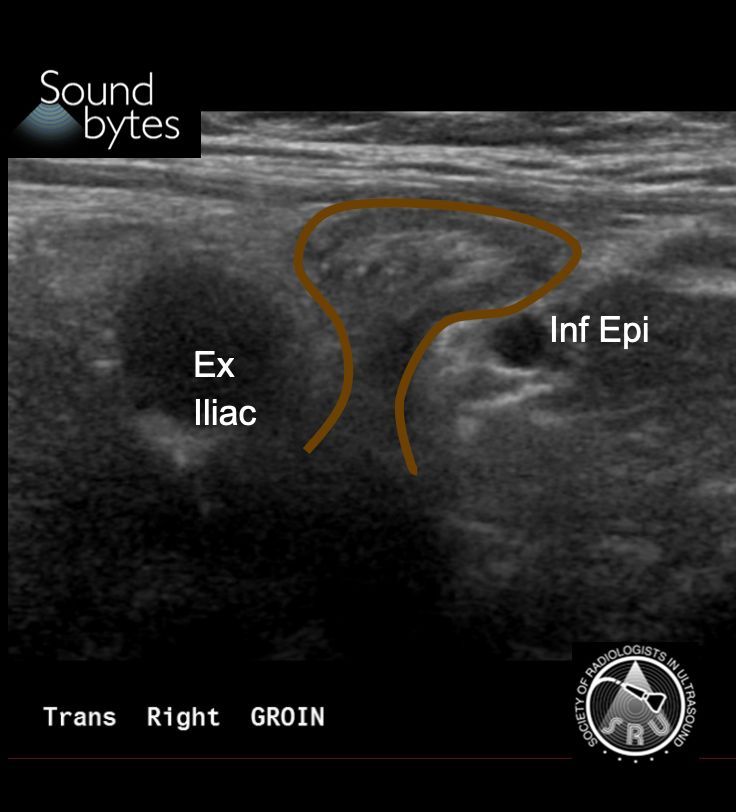

Dx: (Fat containing) *Indirect* Inguinal Hernia

Findings: Herniation of intraabdominal fat between the inferior epigastric and the external iliac vessels.

Man with intermittent palpable and painful lump in the groin. What is your sound diagnosis (be specific)?

Case courtesy of Dr. Neel Patel, OHSU